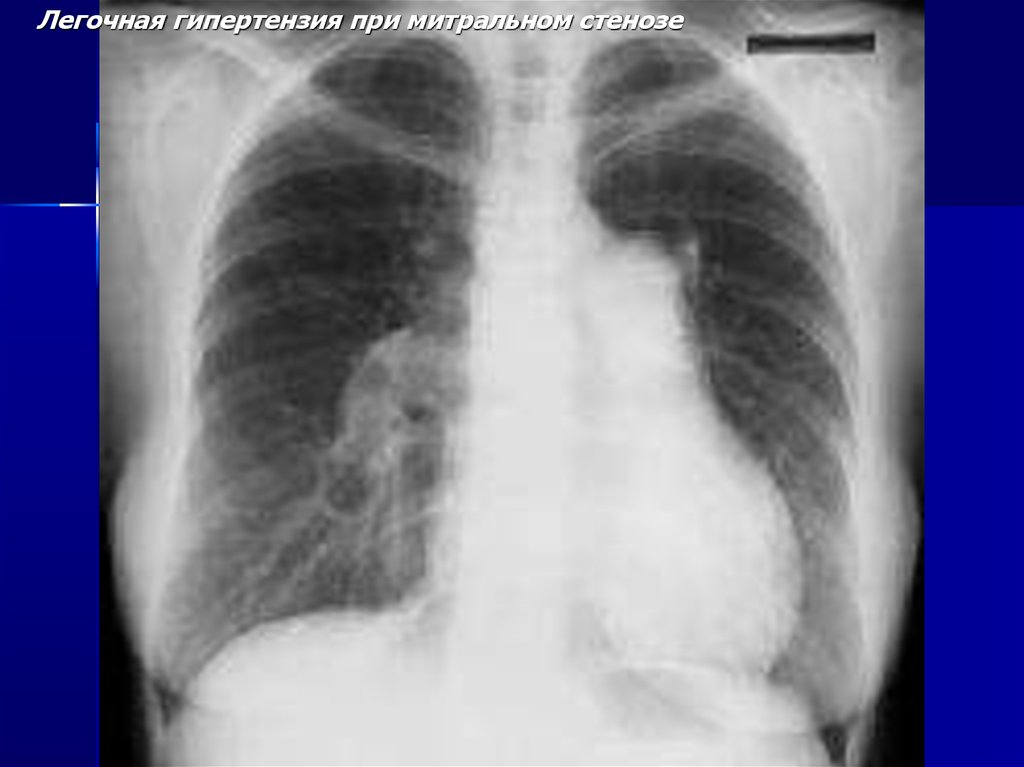

Легочная гипертензия при митральном стенозе